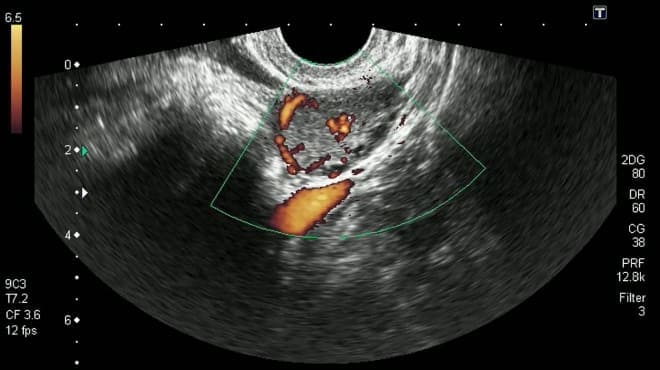

Проблемы с работой кишечника и учащенные позывы к опорожнению мочевого пузыря наблюдаются практически у всех беременных женщин, поэтому только на основании этих признаков невозможно точно установить наличие патологии. Боли в нижней части живота могут указывать на растяжение связок матки. Для точной диагностики патологии необходимо провести УЗИ, которое разрешено на любом сроке беременности.

Для точного определения недостатка прогестерона на фоне наличия новообразования в яичнике необходимо провести УЗИ.

| УЗИ | Позволяет выявить образование на яичниках, а при беременности — увеличенную матку. Плодное яйцо может не быть обнаружено до 5-7 недель гестации из-за его небольших размеров. |

В большинстве случаев лечение кисты не требуется. Женщинам рекомендуется регулярно проходить ультразвуковое обследование и сдавать анализы на уровень прогестерона для мониторинга своего состояния. В некоторых случаях могут быть назначены определенные препараты:

Все медикаменты следует использовать только после консультации с врачом. Перед началом лечения необходимо пройти обследование на уровень гормонов и сделать УЗИ органов малого таза.

Во-первых, регулярные медицинские осмотры и ультразвуковое исследование являются ключевыми для мониторинга состояния женщины и развития беременности. Врач может контролировать размер кисты и её влияние на уровень гормонов, что особенно важно в первом триместре, когда происходит формирование плаценты и гормональная перестройка организма.

В большинстве случаев женщины с кистой жёлтого тела не нуждаются в особом наблюдении, так как это состояние обычно не влияет на течение беременности. Тем не менее, врач может рекомендовать регулярные ультразвуковые исследования для контроля за состоянием кисты и исключения возможных осложнений. Важно следовать рекомендациям специалиста и сообщать о любых изменениях в состоянии здоровья.

Регулярно проходите плановые УЗИ и другие обследования, назначенные вашим врачом. Это поможет контролировать состояние кисты и своевременно выявлять возможные изменения, что особенно важно для здоровья как матери, так и ребенка.